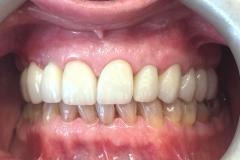

Implant Work by Dr Kevin Bruce:

Full smile rehabilitation involving replacement of missing and failing teeth with implant-supported restorations, combined with aesthetic correction of existing dentition. The treatment was carefully planned to restore function, improve alignment, and achieve a balanced, natural-looking smile.

Implants were strategically placed to support long-term stability, with particular attention to soft tissue contours and emergence profiles to ensure seamless integration with the surrounding teeth. The final restoration was designed to enhance both aesthetics and bite function, delivering a confident and harmonious result.

This case demonstrates a comprehensive approach to implant and restorative dentistry, combining surgical precision with advanced prosthetic design to achieve predictable, long-term outcomes.